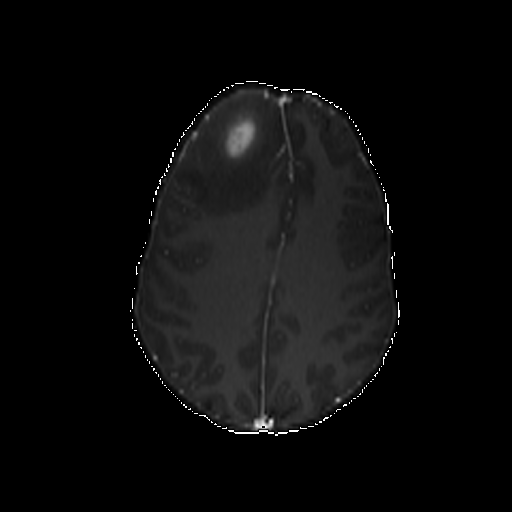

Qualitative evaluation.

To provide a more intuitive observation of our medical vision generalist, we provide the visualization of different tasks in Figure 4.